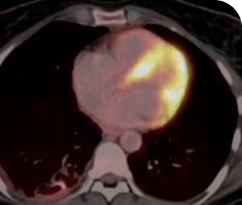

PATIENT CASE:

NSCLCa PATIENT WITH BRAIN

METASTASES1-3

- 76-year-old female with NSCLC that metastasized to the the brain and liver

- No prior systemic treatment before trial enrollment

- PRa of primary lung nodules to VITRAKVI® (larotrectinib) confirmed at 2 months1

Clinical presentation1,2

- Presented with a persistent cough, fatigue, and anorexia

- Imaging identified bilateral lung nodules with metastases to the brain

- Endobronchial biopsy confirmed lung adenocarcinoma

Prior treatments and outcomes3

- No prior surgery or radiation

- Patient elected not to undergo platinum doublet chemotherapy treatment for her lung cancer in front line

Testing1

- Initial DNAa-based NGSa testing was negative for NTRKa gene fusions

- Subsequent RNAa-based NGS testing identified EPS15a-NTRK1 gene fusion

VITRAKVI treatment2

- VITRAKVI 100 mg BIDa orally

Response to VITRAKVI1,2

- Partial response to treatment that was confirmed at 2 months (34% tumor reduction)

- Grade 1 cough and Grade 2 fatigue

- Patient remains on VITRAKVI after more than 4 months of treatment

Response in primary and metastatic lesions1

MRIa imagery of the brain. Green circles indicate baseline brain metastases.1

SCAN 2: BRAIN

aMRI, magnetic resonance imaging.

MRIa imagery of the brain. Green voxels indicate decreased burden of metastatic disease; further quantified by accompanying measurement in green.1

SCAN 3: BRAIN

Pre- and post-treatment imaging, by Rosen EY et al, is licensed under Creative Commons License CC BY 4.0.